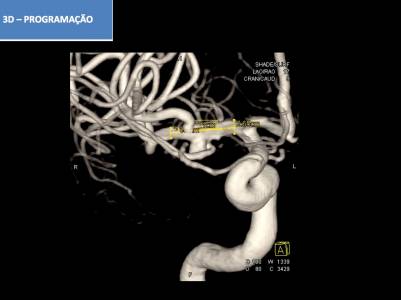

Aneurisma incidental relacionado a artéria cerebral média diagnosticado após investigação de cefaleia. Realizado tentativa de embolização com micromolas sem sucesso, sendo optado pelo tratamendo endovascular com stent redirecionador de fluxo Fred Jr 03 x 14 x 19 mm.